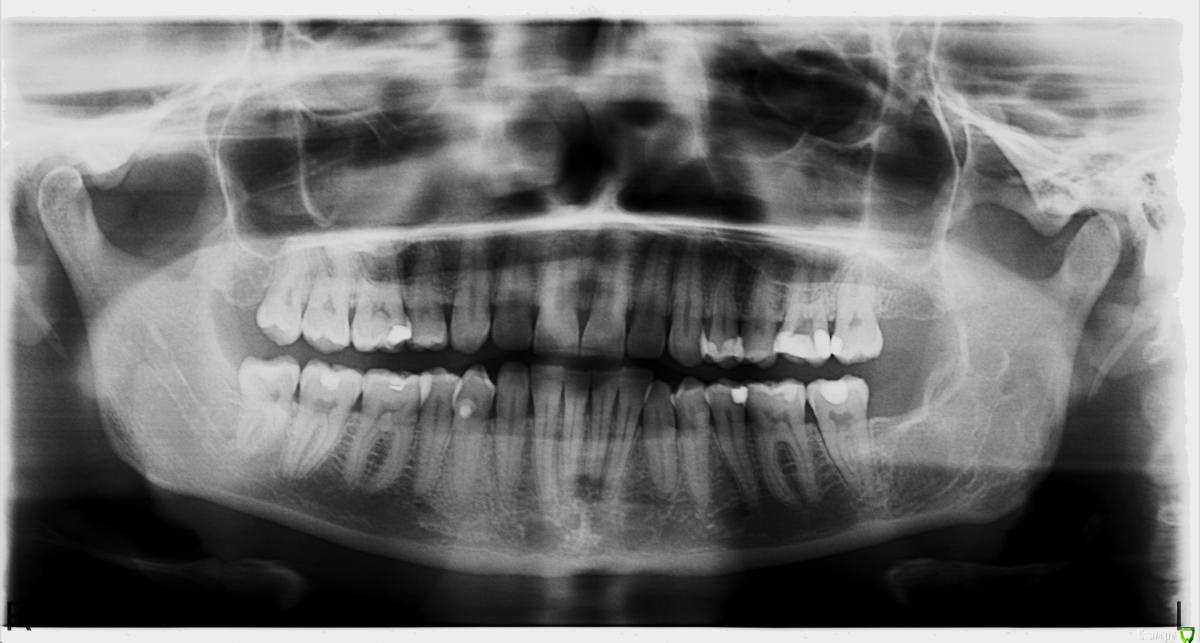

Marinelli30 Опубликовано 12 сентября, 2016 Поделиться Опубликовано 12 сентября, 2016 (изменено) Уважаемые специалисты, Не могли бы вы прокоментировать состояние моих зубов на наличие кист и других отклонений. Интересуют затемнения на снимке в области нижних передних зубов. Была у стоматолога по поводу боли верхнего шестого зуба слева, который был пролечен не раз. Его корни выходили в гайморову пазуху, в которой ранее была диагностирована небольшая киста 0,5 х 2 см. Врач сказал, что по снимку неясно связана ли киста с зубом или нет и зуб в итоге удалил в прошлую среду. Теперь болят соседние зубы при накусывание. Также лечила последние две недели пародантит (амоксицилин и метранидазол), который заработала после лечения зубов. На нижних передних зубах чувство затекания, возможно от перераспредеоения нагрузки после удаления зуба. По нижним передним зубам ничего мне не сказали, хотя я беспокоюсь о затемнениях в этой области на панорамном снимке. Ранее была операция по удалению кисты нижней челюсти (второй снимок). Заранее благодарю за помощь! С уважением,Марина Изменено 12 сентября, 2016 пользователем Marinelli30 Ссылка на комментарий